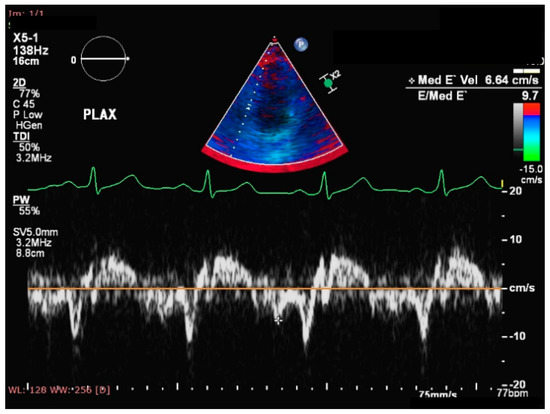

- Esanu, V.; Palii, I.; Mocanu, V.; Vudu, L.; Esanu, V. Left ventricular remodeling patterns in children with metabolic syndrome. One Health Risk Manag. 2020, 1, 41–49. [Google Scholar] [CrossRef]